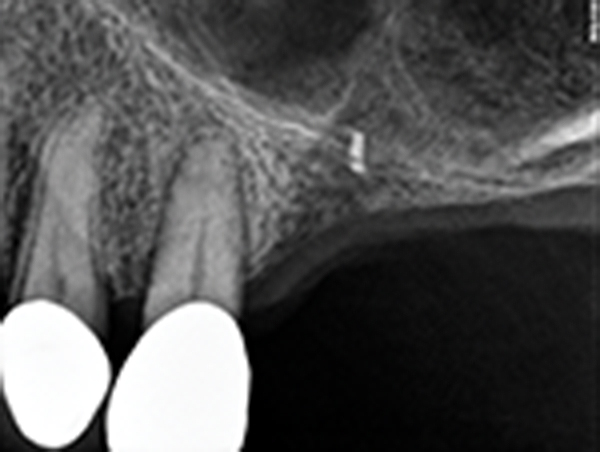

Fig 17. Case 2. Preoperative ridge in the No. 14 position. The height of native bone is about 4 mm to 5 mm.

Figure 17

Fig 18. 16-month postoperative radiograph showing stable bone. The patient refused treatment of tooth No. 15, which has endodontic involvement.

Figure 18

Fig 19. CBCT scan (Kodak 9000D) of implant No. 14 showing homogeneous appearance of the bone.

Figure 19

A 74-year-old male patient presented with about 4 mm to 5 mm of native bone in the No. 4 position (Figure 17). A composite graft, as described in Case 1, was used, as was the same implant type, but the implant was 11.5 mm in length with a taper of 5 mm to 4.2 mm. The approximately 16-month post-healed floor of the sinus was raised about 7 mm to 8 mm (Figure 18). The CBCT scan taken at 16 months postoperatively showed no change in appearance from the area of the old floor of the sinus to the new bone formed (Figure 19). Although it was endodontically involved, tooth No. 15 was not extracted, against professional advice. As can be seen in Figure 18, the No. 14 implant is acting as a bridge abutment.